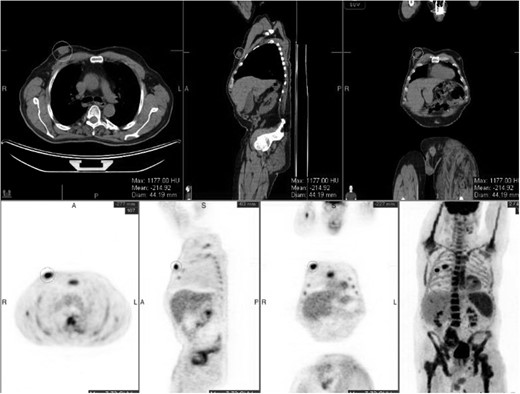

Staging positron emission tomography computed tomography (PET CT) was performed demonstrating activity in the right breast as well as mediastinal and hilar lymphadenopathy (Fig. 2). The patient underwent neoadjuvant chemotherapy and a repeat PET CT showed decreased activity in the right breast and no further lymphadenopathy (Fig. 3). A right modified radical mastectomy was performed. Pathologic examination revealed invasive ductal carcinoma, histologic grade III with closest margin at 1mm away. There was 0 out of 18 positive axillary lymph nodes. Pathologic staging was set at pT2N0M0, Stage IIA. Given the slim posterior margin, he received post mastectomy radiation therapy. Currently, the patient is receiving tamoxifen 20 mg once a day.

Post chemotherapy PET/CT scan. The breast mass decreased in size, with no mediastinal or hilar lymphadenopathy.